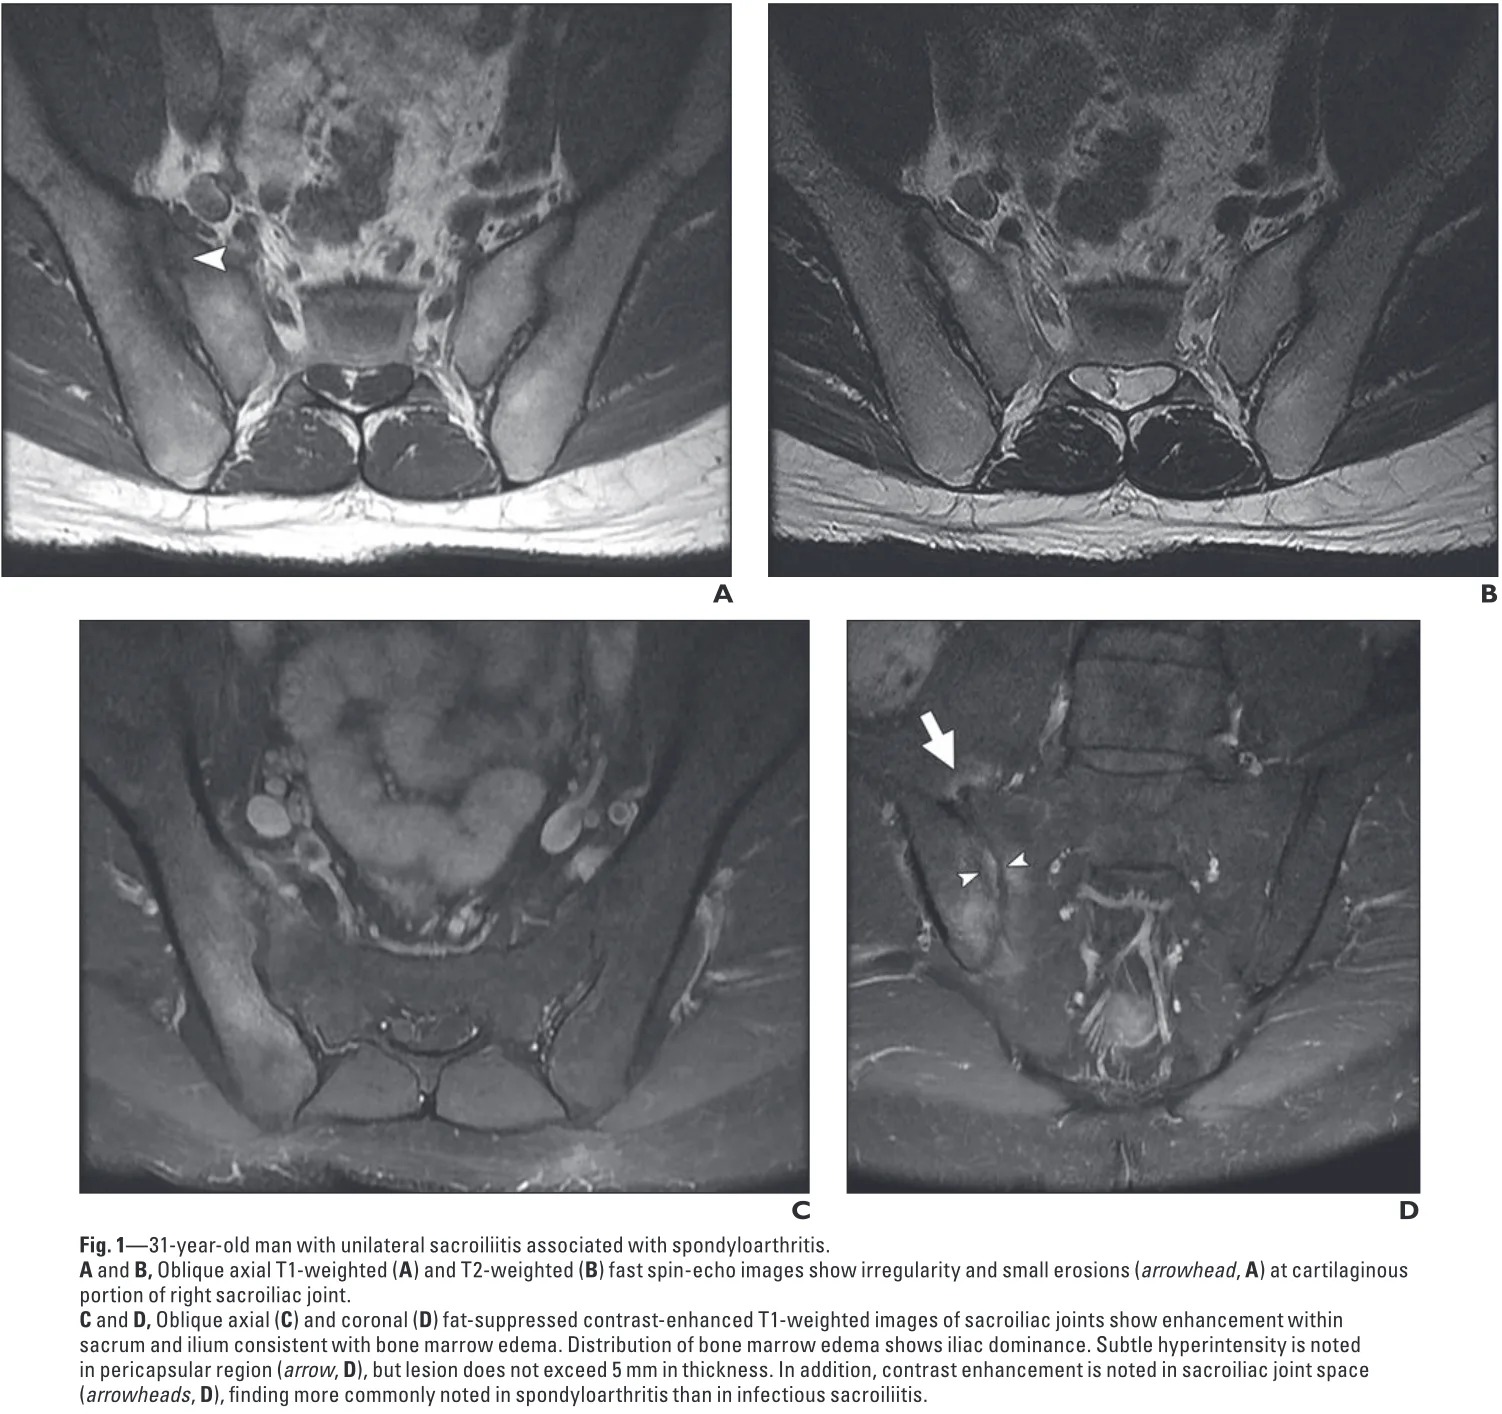

右の仙腸関節部が, T1強調画像(A)では黒く, T2強調画像(B)では白く写っています.

MRIでは, 疼痛側の仙腸関節に明らかな炎症性変化を認めました.

何らかの原因による仙腸関節炎が殿部痛の原因と判断.

仙腸関節炎の代表的疾患としては脊椎関節炎が挙げられますが, 急性発症という点が一致しません.

一方, 細菌感染による仙腸関節炎は見逃してはならないものの, 糖尿病や悪性腫瘍など, 明らかな易感染性因子は認めませんでした.

原因は特定できず, 消炎鎮痛薬ジクロフェナクを処方し, 1週間後に再評価することに.